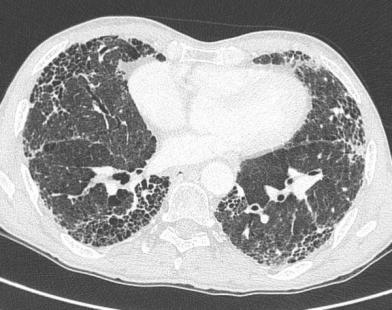

Mr Y vient en consultation pour dyspnée d'effort et toux sèche, à l'examen vous observez des râles crépitants (velcro) aux bases et l'existence d'un hippocratisme digital. Vous observez l'image suivante au scanner :

Quelle est votre principale suspicion ?

Fibrose pulmonaire idiopathique (FIP) :

-grands signes cliniques

-signes de TDM : kystes, réticulations, bronchectasies

-prédominance aux bases des signes (au TDM et les crépitants)